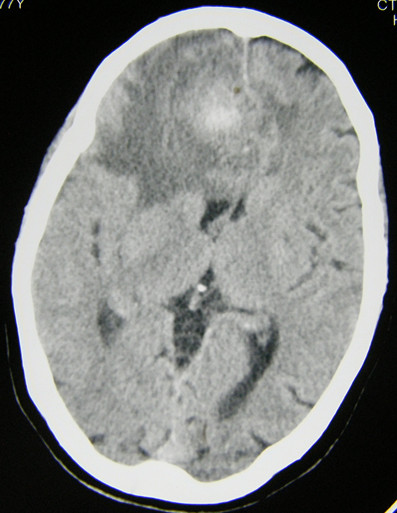

(1)注意识别脑瘤卒中的平扫CT及 MIR片特点:①多为形态不规则密度不均匀的混杂密度病灶,而高血压脑出血多为密度较均匀的类圆形团块状较高密度灶;② 病灶常位于远离中线的脑叶,而高血压脑出血的病灶常位于基底节区及丘脑区;③ 其病灶相对于高血压脑出血病灶的周围水肿比较明显,出血灶周围常有较广泛的大片脑水肿低密度区,而一般脑血肿周围常仅有薄的水肿带;见影像片1,2

影像片1:CT平扫,示形态不规则密度不均匀的混杂密度病灶,位于枕叶及侧脑室枕角处,局部水肿明显。